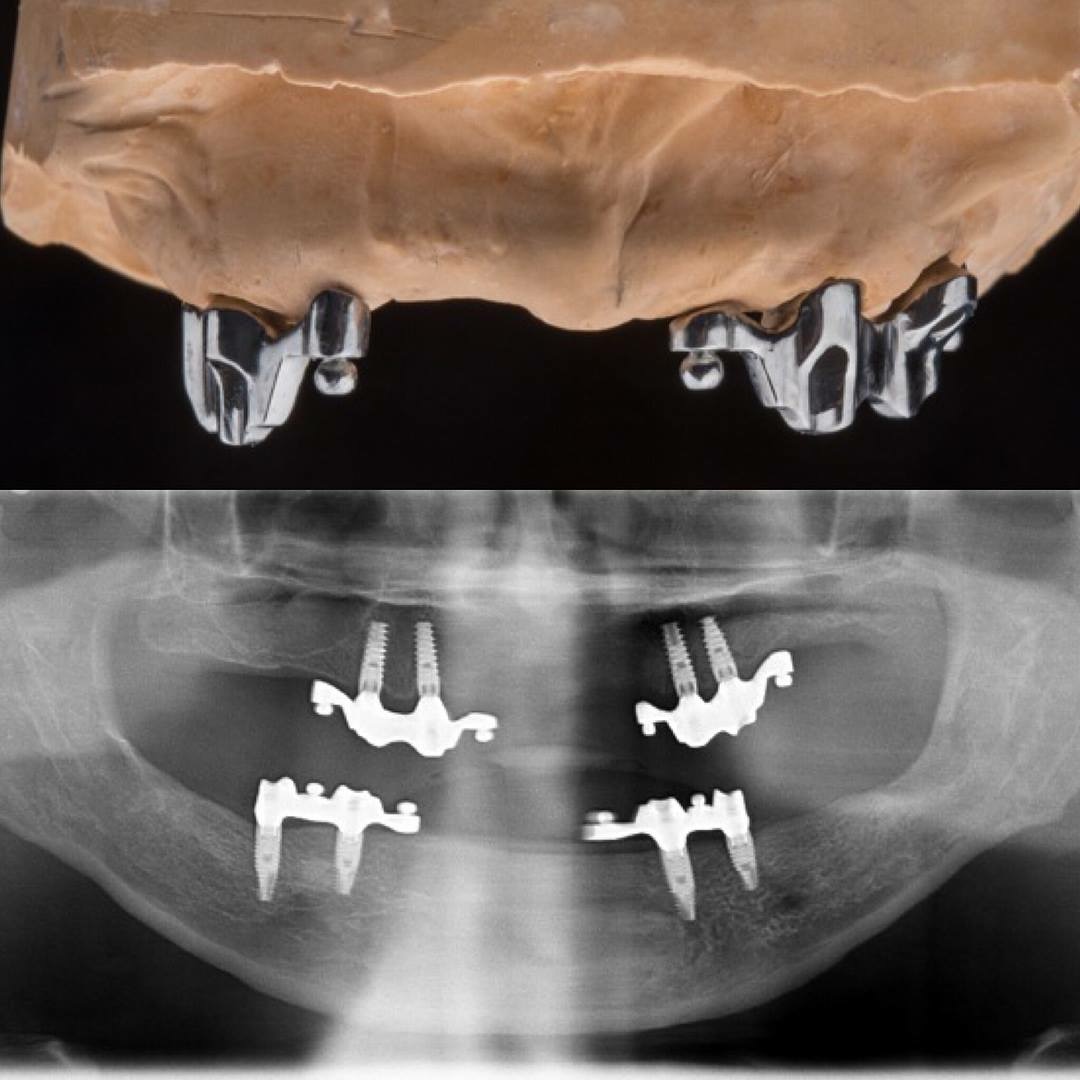

Dr. Ricardo Velázquez García es un dentista destacado en Colima, especializado en implantes dentales y cuidado integral de la salud bucal. Ubicado en el Centro Médico Puerta de Hierro, en Calle Ignacio Sandoval 1699-Consultorio 312, Girasoles, ofrece un ambiente profesional y acogedor para todos sus pacientes. Con una sólida reputación respaldada por una calificación de 5 estrellas basada en 235 opiniones, el Dr. Velázquez se distingue por su atención personalizada y la calidad de sus tratamientos. Sus pacientes valoran especialmente la amabilidad del equipo, la limpieza profunda y los resultados efectivos, como blanqueamientos dentales y procedimientos de bonding. La clínica cuenta con tecnología avanzada y un equipo comprometido en brindar una experiencia cómoda y segura. Para agendar una cita o solicitar información, puede comunicarse al teléfono 312 688 2357 o visitar su sitio web oficial https://dentaldesign.acecli.cloud/. El Dr. Ricardo Velázquez García es una opción confiable para quienes buscan mejorar su sonrisa y mantener una salud dental óptima en Colima.

Dr. Ricardo Velazquez García is a highly regarded dentist in Colima, specializing in dental implants and comprehensive oral health care. Located at Centro Medico Puerta de Hierro, Calle Ignacio Sandoval 1699-Consultorio 312, Girasoles, the clinic provides a professional and welcoming environment for all patients. With a 5-star Google rating from 235 reviews, Dr. Velazquez is known for his personalized approach and high-quality dental treatments. Patients appreciate the friendly and professional staff, thorough cleanings, and effective results including teeth whitening and bonding procedures. The clinic is equipped with advanced technology and a team dedicated to delivering a comfortable and safe experience. To schedule an appointment or request more information, contact the office at 312 688 2357 or visit the official website at https://dentaldesign.acecli.cloud/. Dr. Ricardo Velazquez García is a trusted choice for those seeking to improve their smile and maintain excellent dental health in Colima.